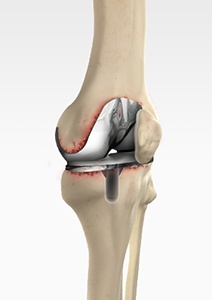

• Complex Primary Knee Replacement

Complex Primary Knee Replacement

Complex primary knee replacement is a joint replacement surgery performed on a severely damaged or deformed natural knee joint.